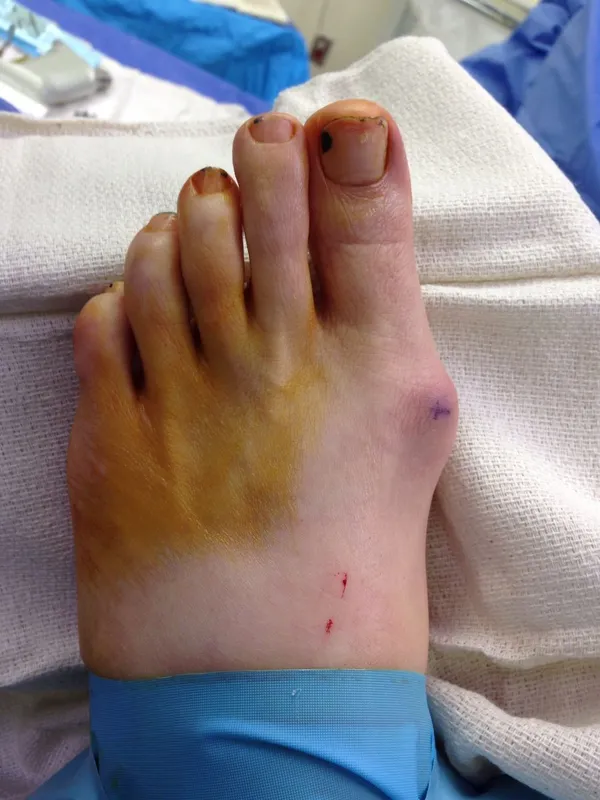

Before and immediately postop S/P bunionectomy

Immediate Postop in OR